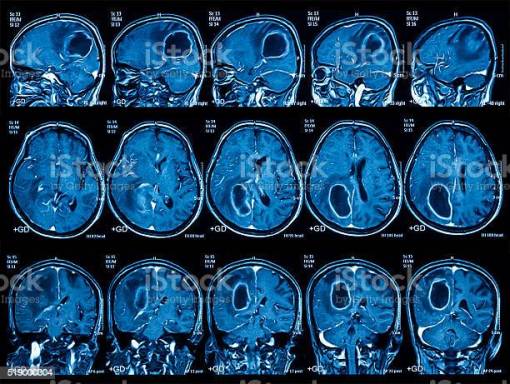

RMN-ul / IRM-ul, dintre toate investigatiile imagistice, detecteaza cel mai bine leziunile mici si obtine imagini detaliate ale acestora in diverse planuri, ceea ce ajuta la localizarea lor, fiind o investigatie foarte utila inaintea interventiilor chirurgicale.

- Investigatii cerebrale - tumori si boli demielinizante la nivelul creierului

- RMN cranio-cerebral

- RMN cranio-cerebral cu angiografie

- RMN cranio-cerebral+hipofizä

- RMN cranio-cerebral orbite

- RMN cranio-cerebral ureche internã